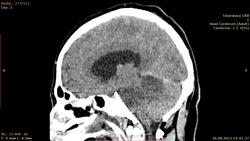

мужчина 1976 г. р. прислали вот такое исследование с направлением "онмк" точка ((( как расценить изменения мозжечка? аномалия?

Какая аномалия? Инфаркт обширный в бассейне основной артерии. Поражены мозжечок со стволом + затылочные доли. Последние поражены в меньшей степени, вследствие компенсации кровотока через ЗСА. Внутренняя тривентрикулярная гидроцефалия. V4 правой позвоночной артерии и основная артерия имеют повышенную плотность, что может соответствовать тромбозу (не всегда). При таких инфарктах обычно бывает окклюзионная гидроцефалия, требующая дренирования желудочковой системы. Тут, по всей видимости, состоянее тяжелое.

Редкостная картина в плане локализации, да еще и с нарастанием отека-опасно.

Какое-то странное симметричное поражение в бассейнах кровоснабжения обеих верхних мозжечковых артерий. Почему нет изменений в бассейнах нижних мозжечковых артерий? Как это объяснить?

Так объясняется анатомией. Отхождение передних и задних нижних мозжечковых артерий (AICA, PICA) проксимальнее уровня поражения и наоборот - поражение выше уровня отхождения описанных артерий.

Получается, что тромбирование (окклюзия) базиллярной артерии произошло дистальнее отхождения передних нижних мозжечковых артерий. Спасибо за презентацию.